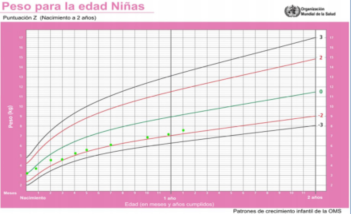

El crecimiento en peso, longitud y perímetro craneano según la edad se muestran en las (Figura 1), (Figura 2) y (Figura 3). En la (Figura 4) se muestra la evolución del peso de acuerdo a la longitud.

Figura 1: Gráfica del peso para la edad. Los puntos verdes indican los valores para esta paciente de acuerdo a la edad.

La antropometría en el momento de la consulta evidenció: peso de 8 kg (score Z del índice antropométrico peso para la edad -1,7); longitud de 68 cm (score Z de longitud para la edad -3,3). La relación peso/longitud tenía un score Z de 0,27. El perímetro cefálico era de 47 cm (score Z 0,55).

La afectación del peso con longitud/talla normal orienta a enfermedad sistémica o déficit nutricional, con incremento de peso orienta a patología endocrinológica9. En esta paciente hubo un cambio en la velocidad de crecimiento de peso y longitud al mismo tiempo, de tal forma que la relación peso/longitud se mantuvo en el mismo carril (figura 4).

En los primeros dos años de vida se alcanza el carril de crecimiento que corresponde a la carga genética. Posteriormente y hasta el inicio del desarrollo puberal, no es habitual cambiar de carril de crecimiento. Si esto sucede, amerita una evaluación exhaustiva. Luego de los 2 años no debieran producirse cambios en la curva de crecimiento mayores a 0,25 DE/año9. Los niños pequeños para la edad gestacional pueden ser una excepción a esta afirmación2,5,13. En el caso presentado se evidenció una desaceleración del crecimiento desde el sexto mes de vida.